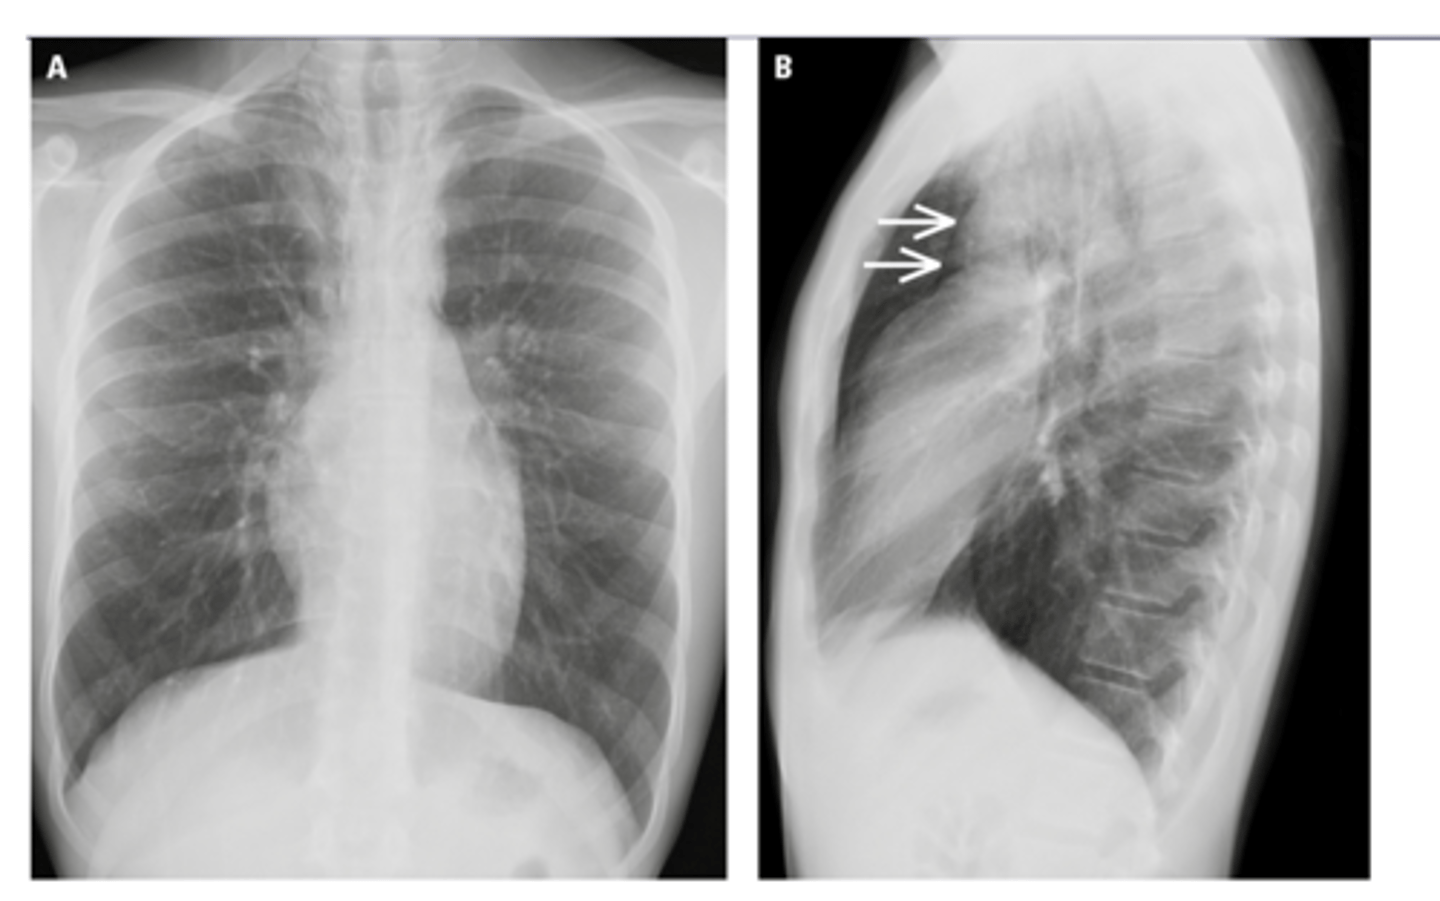

8

New cards

-Flattening of hemidiaphragms with blunting of costophrenic angles.

-Increased AP diameter of chest on lateral view (barrel chest)

-Presence of bullae or large air cavities

What x-ray findings are found in advanced stages of COPD/emphysema?

9

Flattened diaphragms, ant mediastinal space increased --> COPD/emphysema

Dx and ID radiological findings

<p>Dx and ID radiological findings</p>